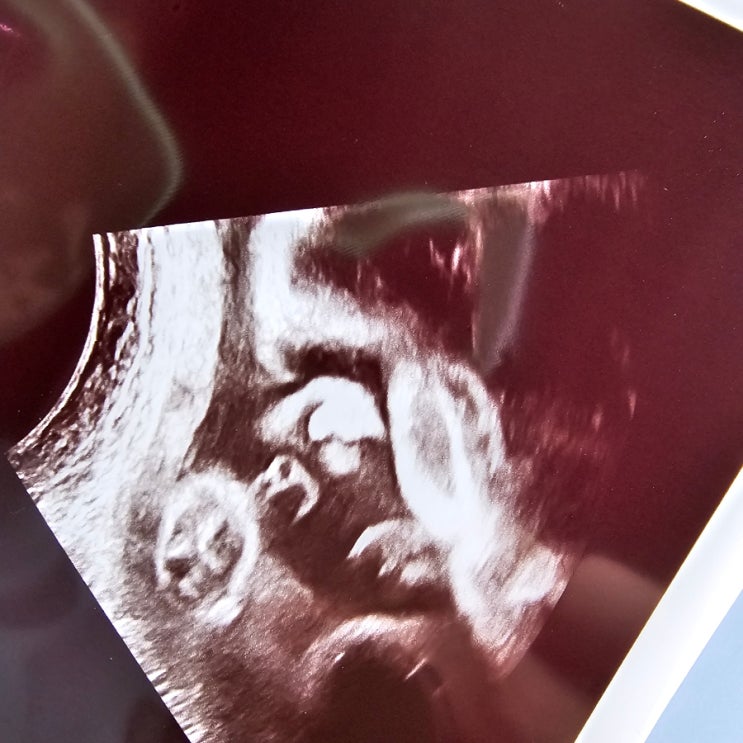

둘째)임신27주 아들 입체초음파,철분부족 약바꾸기

입체초음파 초코없이도 잘 보였어 둘째)임신27주 아들 입체초음파보고 왔는데 첫째랑 닮았다 하는 식구들 ...